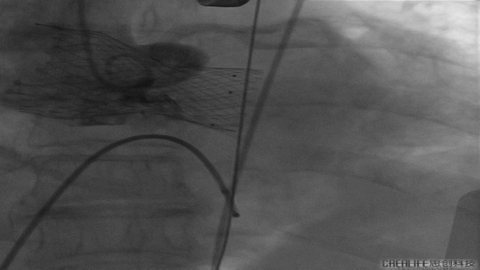

VenusA26号完全释放

最后一枪造影

超声显示人工瓣膜工作良好,微量瓣周漏,术后一周顺利出院,术后随访无并发症,恢复良好。